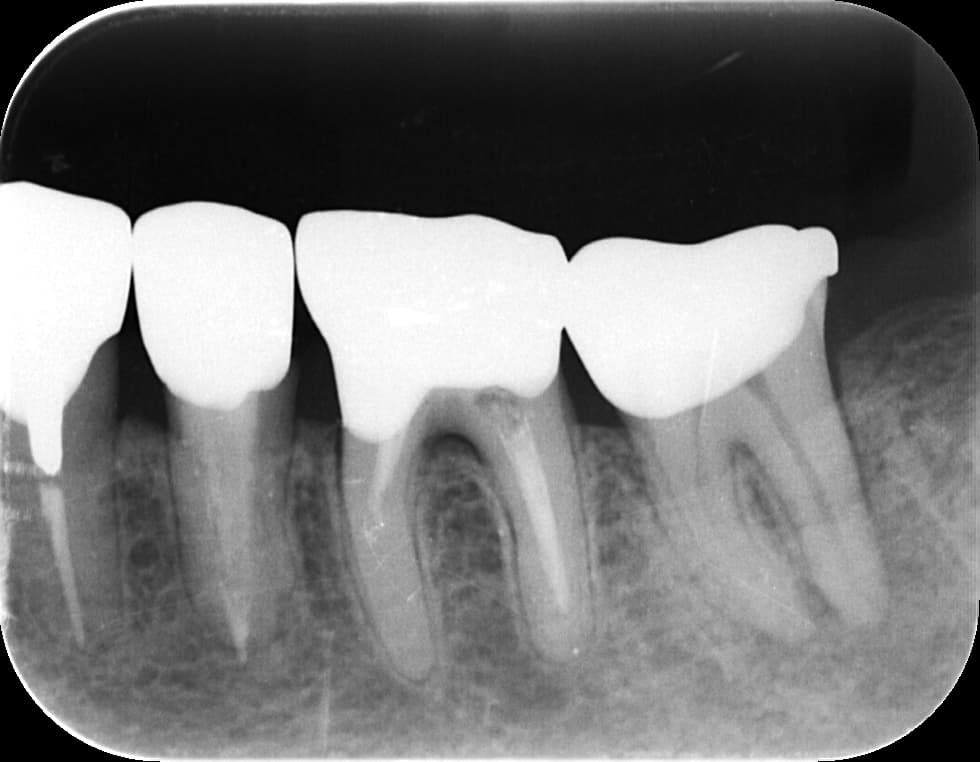

3. 矯正治療前に根管治療を済ませたほうがよい理由

矯正中は歯が動くため、弱っている歯や神経が炎症を起こしやすい時期です。特に、以下のような歯は矯正前に治療した方が安心です。

・大きな虫歯がある

・神経まで深い虫歯が近い

・すでに痛みを繰り返している

・歯髄の炎症が疑われる

・過去の治療が不十分

このような歯をそのまま矯正に進むと、矯正中に 「急に痛みが出る」「歯がしみる」「咬めない」 といったトラブルが発生しやすくなります。

矯正中は器具がついているため治療が難しくなり、治療計画全体が遅れるケースもあります。

そのため、矯正前に “怪しい歯は先に治療しておく” ことが、矯正期間をスムーズに進めるための重要な準備です。